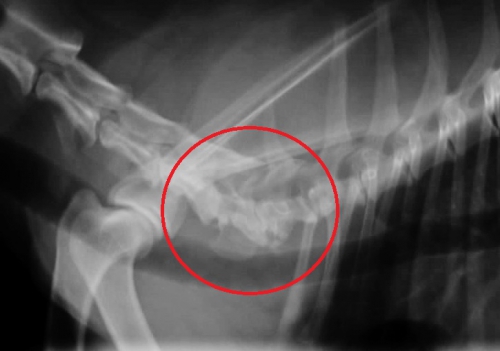

下の写真は日常的に常に頸部の痛みを訴えており、前足の歩行にも問題を生じている患者さんの重度の頸椎~胸椎の変形性脊椎症のレントゲン写真です。

左下の写真、赤丸の中に病変があり、各々の椎骨は両端が大きく変形しております。右下写真は同じ部位の正常なレントゲン写真です。左右の赤丸内の骨の変形が大きいのがお分かりになるかと思います。